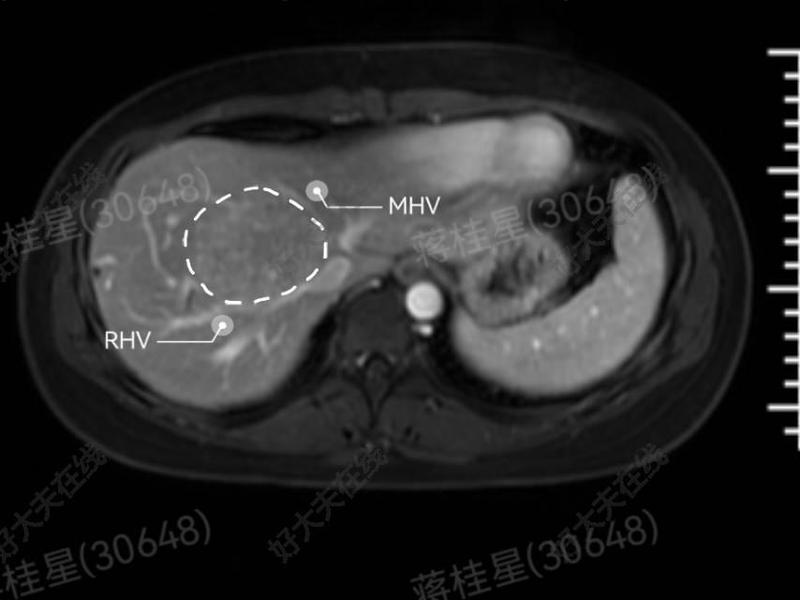

治療前20多歲未婚女性,肝臟FNH近一年明顯增大,腫物位置特殊,手術(shù)切除難度大治療中行腹腔鏡下肝腫物切除治療后治療后7天20多歲的未婚女性,困難部位的肝臟FNH,8月5日行腹腔鏡下腫塊剜除,避免了腹部巨大切口,這個(gè)幾乎看不到的手術(shù)疤痕對(duì)未婚女性意義尤為重大,今天開(kāi)心出院